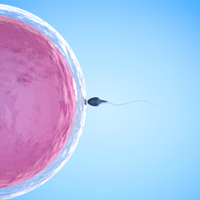

卵泡才发育到12×11大小同房怀孕了就需要到医院进行血检HCG检查,以此来确定自己是真的 怀孕了接下来就需要做好孕期的一些相关事宜。卵泡在没有发育成熟时也有一定的受孕几率,如果在排卵期同房那么自然怀孕的几率是非常大的。在怀孕之后做相关检查是为了确保妊娠期的胎儿和孕妇一切健康,否则的话就会考虑引产准备下一次自然怀孕。当卵泡只发育到12×11大小时,容易让人感到意外,毕竟在临床上发育成熟的卵泡才能够更

卵泡发育到21×19mm时跳绳就破了主要是卵泡已经趋近于发育成熟的状态,此时跳绳会增加破裂的几率,但并不是所有的女性在跳绳后都会发生卵泡破裂的情况。成熟的卵子基本是发育到18-25mm左右的卵泡,在自然状态下或者是外界的影响下会逐渐破裂。如果卵泡发育到成熟的状态下没有自行破裂的话外力的强度运动可能会导致卵泡破裂,但并不是每个人都会出现这种现象。卵泡是女性生殖系统中的一个重要组成部分,它负责孕育和释

正常女性每个月都会有一个卵泡发育成熟,然后破裂排出卵子,当卵子跟精子结合在一起了以后就会形成受精卵。所以很多备孕的女性为了可以加快怀孕的速度,一般会通过监测卵泡的方式了解卵泡发育,那么,排卵期b超看不到卵泡但有积液怎么回事呢?排卵期b超看不到卵泡但有积液如果b超检查显示没有卵泡,但是有盆腔积液,应该是卵泡已经排干净;如果既没有积液也没有卵泡,应该是卵泡没有发育。建议最好在下个月排卵期前几天,隔天做